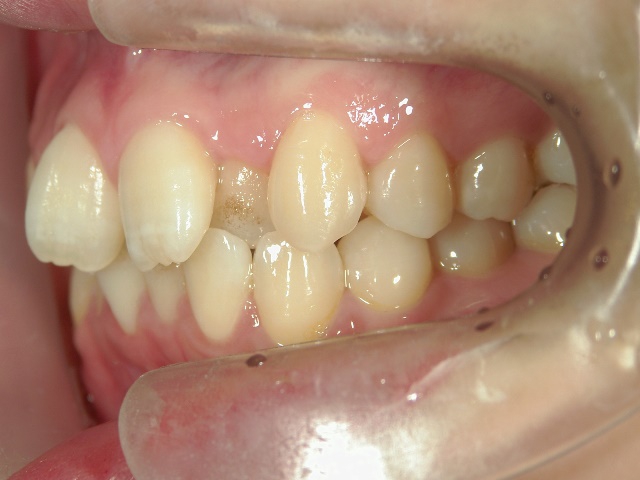

矯正歯科 治療前矯正歯科 治療前

矯正歯科 治療前

no.8_8495_治療前_左.jpgno.8_8495_治療前_正面.jpgno.8_8495_治療前_右.jpg